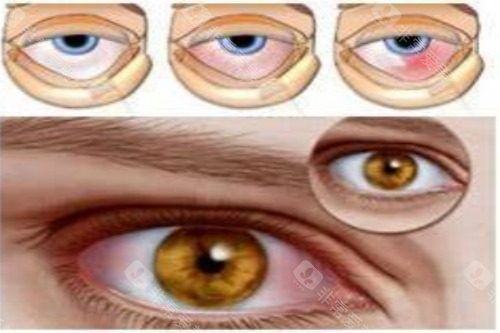

手术可行性均达98%,但博鳌医院因使用术中OCT导航,瞳孔居中率比海口高12个百分点。